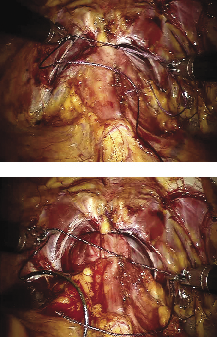

Posterior reconstruction

Posterior reconstruction helps create a posterior plate in which to buffer the anastamosis and reduce bleeding, see Figure 4. Several studies have shown that a proper posterior reconstruction reduces urinary leaks and could also help promote earlier return to pad-free continence.8,9

Figure 4. Posterior reconstruction. A. The VLOC suture is passed through the bladder-side retrotrigonal area at the 5, 6 and 7 o’clock position and through the periurethral rectourethralis muscle. B. Traction is used on the VLOC suture to cinch down the bladder until its mucosa is adjacent to the urethral stump and no gap is left.